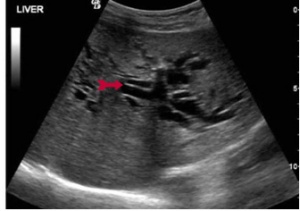

באולטרה-סאונד אפשר להדגים את דרכי המרה החוץ והתוך-כבדיות (תצלום 28.8).

| תצלום 28.8: סונר המראה הרחבה של דרכי המרה התוך כבדיות (מימין) וצינור המרה המשותף (משמאל). | |